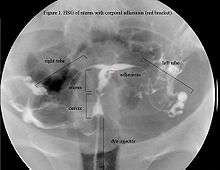

HSG view. Note: not the same uterus as in ultrasound or hysteroscopic view; this uterus appears to be T-shaped.

The cavity of the uterus is lined by the endometrium. This lining is composed of two layers, the functional layer (adjacent to the uterine cavity) which is shed during menstruation and an underlying basal layer (adjacent to the myometrium), which is necessary for regenerating the functional layer. Trauma to the basal layer, typically after a dilation and curettage (D&C) performed after a miscarriage, or delivery, or for surgical termination of pregnancy, can lead to the development of intrauterine scars resulting in adhesions that can obliterate the cavity to varying degrees. In the extreme, the whole cavity can be scarred and occluded. Even with relatively few scars, the endometrium may fail to respond to estrogen. Often, patients experience secondary menstrual irregularities characterized by a decrease in flow and duration of bleeding (amenorrhea, hypomenorrhea, or oligomenorrhea)[6] and become infertile. Menstrual anomalies are often but not always correlated with severity: adhesions restricted to only the cervix or lower uterus may block menstruation. Pain during menstruation and ovulation is sometimes experienced and can be attributed to blockages. It has been reported that 88% of AS cases occur after a D&C is performed on a recently pregnant uterus, following a missed or incomplete miscarriage, birth, or during an elective termination (abortion) to remove retained products of conception.[1]